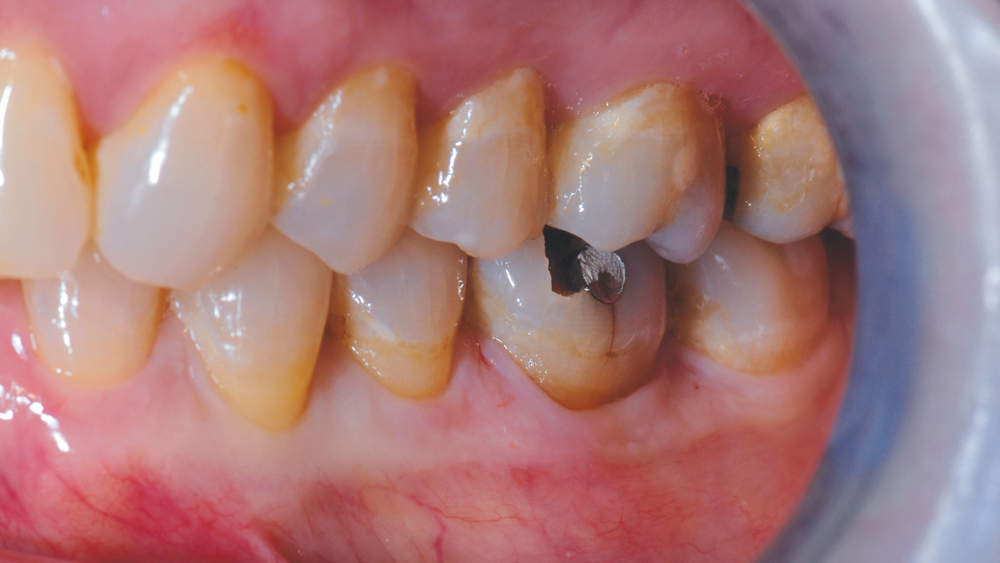

CASE REPORT

The following case highlights the efficient, user-friendly scanning capabilities of the iTero Element scanner, as well as the clinical advantages of connecting to the glidewell.io In-Office Solution for single-appointment dental restorations. The patient sought treatment for a damaged mandibular first molar with a cusp fracture. Because the case called for a single crown and high-strength zirconia, the patient was an ideal candidate for a same-visit restoration milled from a BruxZir NOW milling block. After preparing the tooth and taking an intraoral scan, the crown was fabricated within 40 minutes using the fastmill.io In-Office Unit. The final restoration fit perfectly without adjustment and exceeded the expectations of the patient, who was thrilled that she didn’t have to schedule a second appointment for the crown delivery.